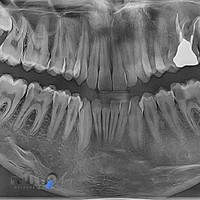

رادیولوژی تا کنون یکی از مهم ترین اقدامات جهت تصویر برداری از نقاط مختلف دهان بوده و نقش بسیاری زیادی در تشخیص وضعیت بدن و لایه های درونی آن ایفا کرده است. نقش رادیولوژی به خصوص در حوزه هایی مانند دندان پزشکی بسیار برجسته است چرا که همانطور که می دانید پیش از هر عملی در این زمینه از شما عکس رادیولوژی خواسته می شود. اگر برای تشخیص بیماری یا چک کردن وضعیت دهان و دندان خود به یک مرکز رادیولوژی دهان و دندان در شهرکرد ارجاع داده شده اید می توانید از این صفحه در این زمینه بهره بگیرید. کافیست با ما همراه باشید و بهترین مرکز رادیولوژی دهان و دندان در شهرکرد را پیدا کنید. در این صفحه برای ساکنین شهرکرد لیستی از بهترین مراکز رادیولوژی دهان و دندان در شهرکرد قرار داده شده است که به سادگی می توانید از بین آن دست به انتخاب بزنید.